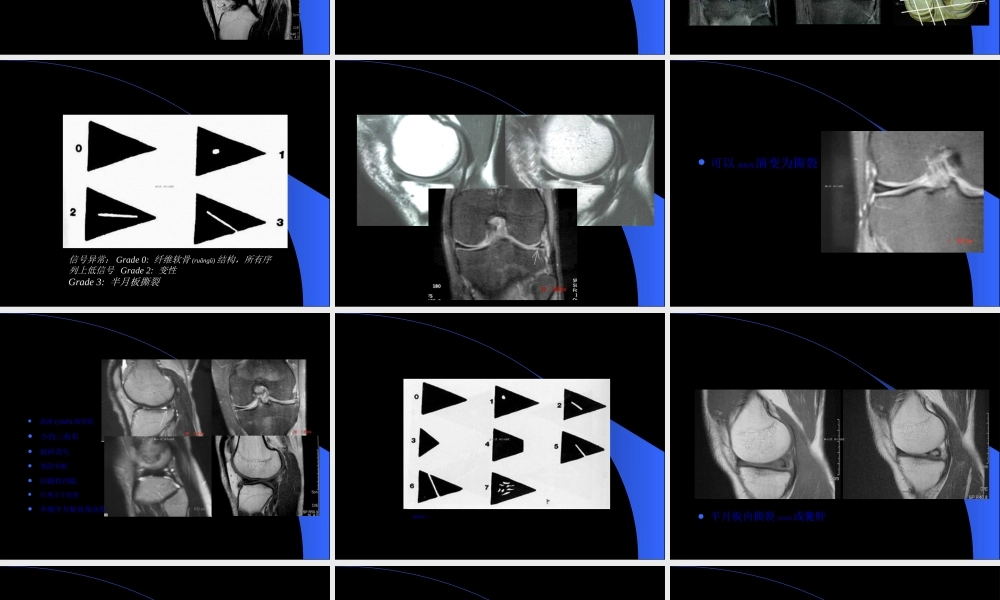

MRIMRI在膝关节创伤在膝关节创伤(chuāngshāng)(chuāngshāng)的应用的应用第一页,共六十四页。第一页,共六十四页。膝关节创伤的MRI半月板病变韧带(rèndài)病变软骨病变其它第二页,共六十四页。第二页,共六十四页。半月板-解剖纤维软骨结构LM:类圆形(O),前后部分(bùfen)相对等宽–外周疏松连接,外后腘肌腱和鞘与关节囊分开–半月板股骨韧带MM:半圆形(C),后部比前部宽–外周与关节囊紧密连接10MM10MM3LM3LM2ACL2ACL8PCL8PCL第三页,共六十四页。第三页,共六十四页。横韧带连接2个半月板前角位置(wèizhi):–关节囊之前–Hoffa’s髌下脂肪后部出现率:矢状面64%厚度:可变11横韧带横韧带22和和33半月板股骨半月板股骨(gǔgǔ)(gǔgǔ)韧韧带带((HumphreyandWrisbergHumphreyandWrisberg韧带)韧带)44腘肌腱腘肌腱55和和6ACL,PCL6ACL,PCL第四页,共六十四页。第四页,共六十四页。半月板股骨韧带LM后角—股骨内髁–Humphrey韧带(rèndài):PCL之前–Wrisberg韧带:PCL之后–出现率单个出现>1/3以上同时出现率6-20%第五页,共六十四页。第五页,共六十四页。半月板-技术考虑矢状位和冠状位短TE图像(túxiànɡ)优于长TE图像(túxiànɡ)-T1WI,PDWI,GRE优于T2WI第六页,共六十四页。第六页,共六十四页。正常半月板断层表现第七页,共六十四页。第七页,共六十四页。半月板撕裂诊断标准信号异常:信号异常:Grade0:Grade0:纤维软骨纤维软骨(ruǎngǔ)(ruǎngǔ)结构,所有序结构,所有序列上低信号列上低信号Grade2:Grade2:变性变性Grade3:Grade3:半月板撕裂半月板撕裂第八页,共六十四页。第八页,共六十四页。半月板撕裂-Grade3信号第九页,共六十四页。第九页,共六十四页。半月板-Grade2信号可以(kěyǐ)演变为撕裂第十页,共六十四页。第十页,共六十四页。半月板撕裂-形态异常游离(yóulí)缘变钝小的三角形破碎消失领结中断局限性凹陷后角小于前角外侧半月板前角高度>6mm第十一页,共六十四页。第十一页,共六十四页。半月板撕裂诊断标准同时考虑(kǎolǜ)信号和形态的改变第十二页,共六十四页。第十二页,共六十四页。半月板特殊信号异常半月板内撕裂(sīliè)或囊肿第十三页,共六十四页。第十三页,共六十四页。半月板撕裂分类层裂斜裂纵裂(zònɡliè)放射状撕裂注注:MR:MR的作用的作用(zuòyòng)(zuòyòng)在于明确有无撕裂,对撕裂的分型能在于明确有无...